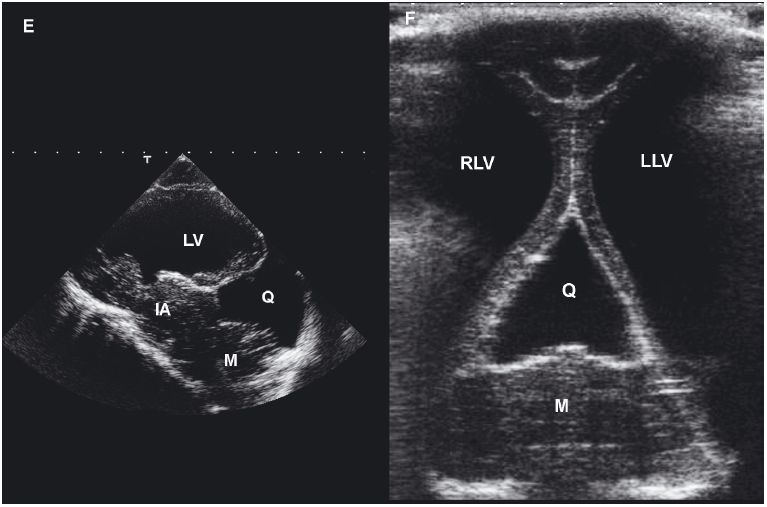

Choroid plexus cysts, intracranial arachnoid cysts, and epidermoid and dermoid cysts associated with the fourth ventricle, quadrigeminal cistern, or cerebellopontine angle have been reported. Arachnoid cysts are seen most commonly in the quadrigeminal cistern, where they appear as a well-defined anechoic mass between the caudal aspect of the cerebral hemispheres. The midbrain will be found ventral to the cyst, and the cerebellum will be caudal (Saito et al. 2001). Congenital cysts secondary to abnormal development or destruction of brain parenchyma, such as in Dandy-Walker syndrome and porencephaly or hydranencephaly, can also occur. Hydranencephaly is diagnosed when the cerebral hemispheres are absent or almost completely absent (Cruz et al. 2003).

Figure 1.18. Cyst in the cerebellum of an 8-year-old terrier. The cyst was drained surgically, but an astrocytoma was later diagnosed at the site (as seen in Figure 1.13). A and B: Sagittal and dorsal postcontrast T1-weighted images of the brain on which a well-defined, hypointense cystlike lesion is identified (*). C: Transverse sonogram of the cerebellum imaged from the foramen magnum on which the cyst appears as a well-defined, oval, anechoic lesion (*). D: Longitudinal sonogram of the cyst. The bone of the skull and vertebral column prevents visualization of portions of the brain and spine, but the part of the brain (arrowheads) can be seen through the foramen magnum. A portion of the spinal cord (SC) can also be observed as it joins the medulla oblongata (M) rostrally. Cursors have been placed to measure the cyst in the cerebellum. Images courtesy of D. Penninck and S. Hecht. E and F: Sonograms of a 1-year-old Chihuahua with hydrocephalus and a quadrigeminal cyst. E: Sagittal sonogram showing the quadrigeminal cyst (Q) and confluence of the dilated lateral ventricles (LV). F: Transverse sonogram. LLV, left lateral ventricle; M, midbrain; and RLV, right lateral ventricle. Images courtesy of B. Poteet, Gulf Coast Veterinary Specialists, Houston.